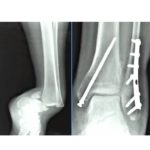

Ankle fractures: Radiologic Evaluation

Courtesy: Saqib Rehman MD

Director of Orthopaedic Trauma

Temple University

Philadelphia

Pennsylvania

USA

Ankle fracture initial evaluation